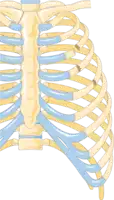

Illustration showing rib fracture at 3rd, 4th and 5th rib